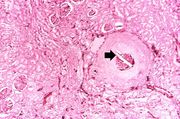

| 21:48, 20 August 2013 | IPLab6ChronicRejection1.jpg (file) | 43 KB | This is a low-power photomicrograph of the kidney from this case of chronic transplant rejection. Note the focal areas of hemorrhage and inflammatory cell infiltrate in this section. | 1 | |